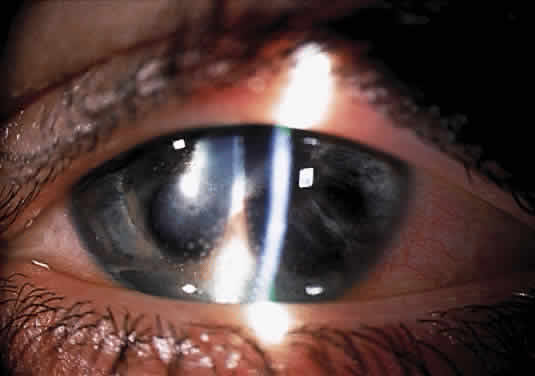

Herpetic keratouveitis can occur in association with any form of herpetic keratitis. Anterior chamber inflammation that accompanies epithelial disease is thought to be caused by reflex irritation and is characteristically both mild and transient. However, the iridocyclitis that invariably accompanies necrotizing disease tends to be much more severe, and is not necessarily correlated with the apparent severity of the keratitis. Indeed, although uveitis dominates the clinical picture in some cases of ocular HSV, subtle corneal findings are limited to faint cellular infiltration of the stroma. Uveitis that accompanies necrotizing disease is typically granulomatous and often recurrent. In more severe cases, perilimbal injection is marked, and the cornea can become thickened and edematous. Dense, fibrinous flare with heavy, anterior chamber cell and medium-sized white keratic precipitates may be distributed widely over the endothelium (Fig. 2). A hypopyon and synechiae can form, and elevated intraocular pressure that exacerbates this often painful uveitis may develop. Marked dilation of iris blood vessels and spontaneous hyphemas sometimes occur. Episodes of inflammation are frequently marked by progressive iris atrophy and sphincter damage, leading to corectopia and anisocoria (Figs. 3 and 4).